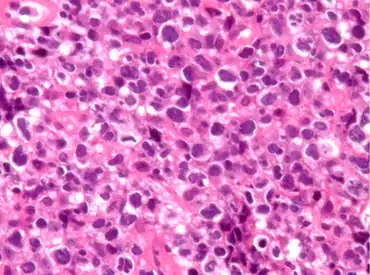

| Pathological features observed during staining. | |

PMLBCL arises from a putative thymic peripheral B cell.[3][4] It has several distinctive biological features.[3] Molecular analysis shows that PMLBCL is distinct from other types of diffuse large B-cell lymphomas (DLBCL).[4] MAL gene expression is seen in 70%, unlike other diffuse large B-cell lymphomas.[2]: 370 Gene expression profiling shows considerable variance from other DLBCLs and similarity to Hodgkin disease.[5]: 290–293

PMLBCL is CD20 positive, expresses pan-B markers including CD79a, and has clonal immunoglobulin gene rearrangements and mRNA but paradoxically does not express cytoplasmic or cell surface immunoglobulin.[2]: 370